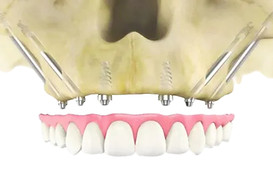

Zygomatic implants are a game-changer for patients with severe bone loss, but mastering this advanced technique requires specialized training. With so many courses available globally, choosing the right one can be challenging.